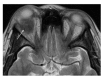

Orbital inflammatory disease (OID) represents a collection of inflammatory conditions affecting the orbit. OID is a diagnosis of exclusion, with the differential diagnosis including infection, systemic inflammatory conditions, and neoplasms, among other conditions. Inflammatory conditions in OID include dacryoadenitis, myositis, cellulitis, optic perineuritis, periscleritis, orbital apicitis, and a focal mass. Sclerosing orbital inflammation is a rare condition with a chronic, indolent course involving dense fibrosis and lymphocytic infiltrate. Previously thought to be along the spectrum of OID, it is now considered a distinct pathologic entity. Imaging plays an important role in elucidating any underlying etiology behind orbital inflammation and is critical for ruling out other conditions prior to a definitive diagnosis of OID. In this review, we will explore the common sites of involvement by OID and discuss differential diagnosis by site and key imaging findings for each condition.